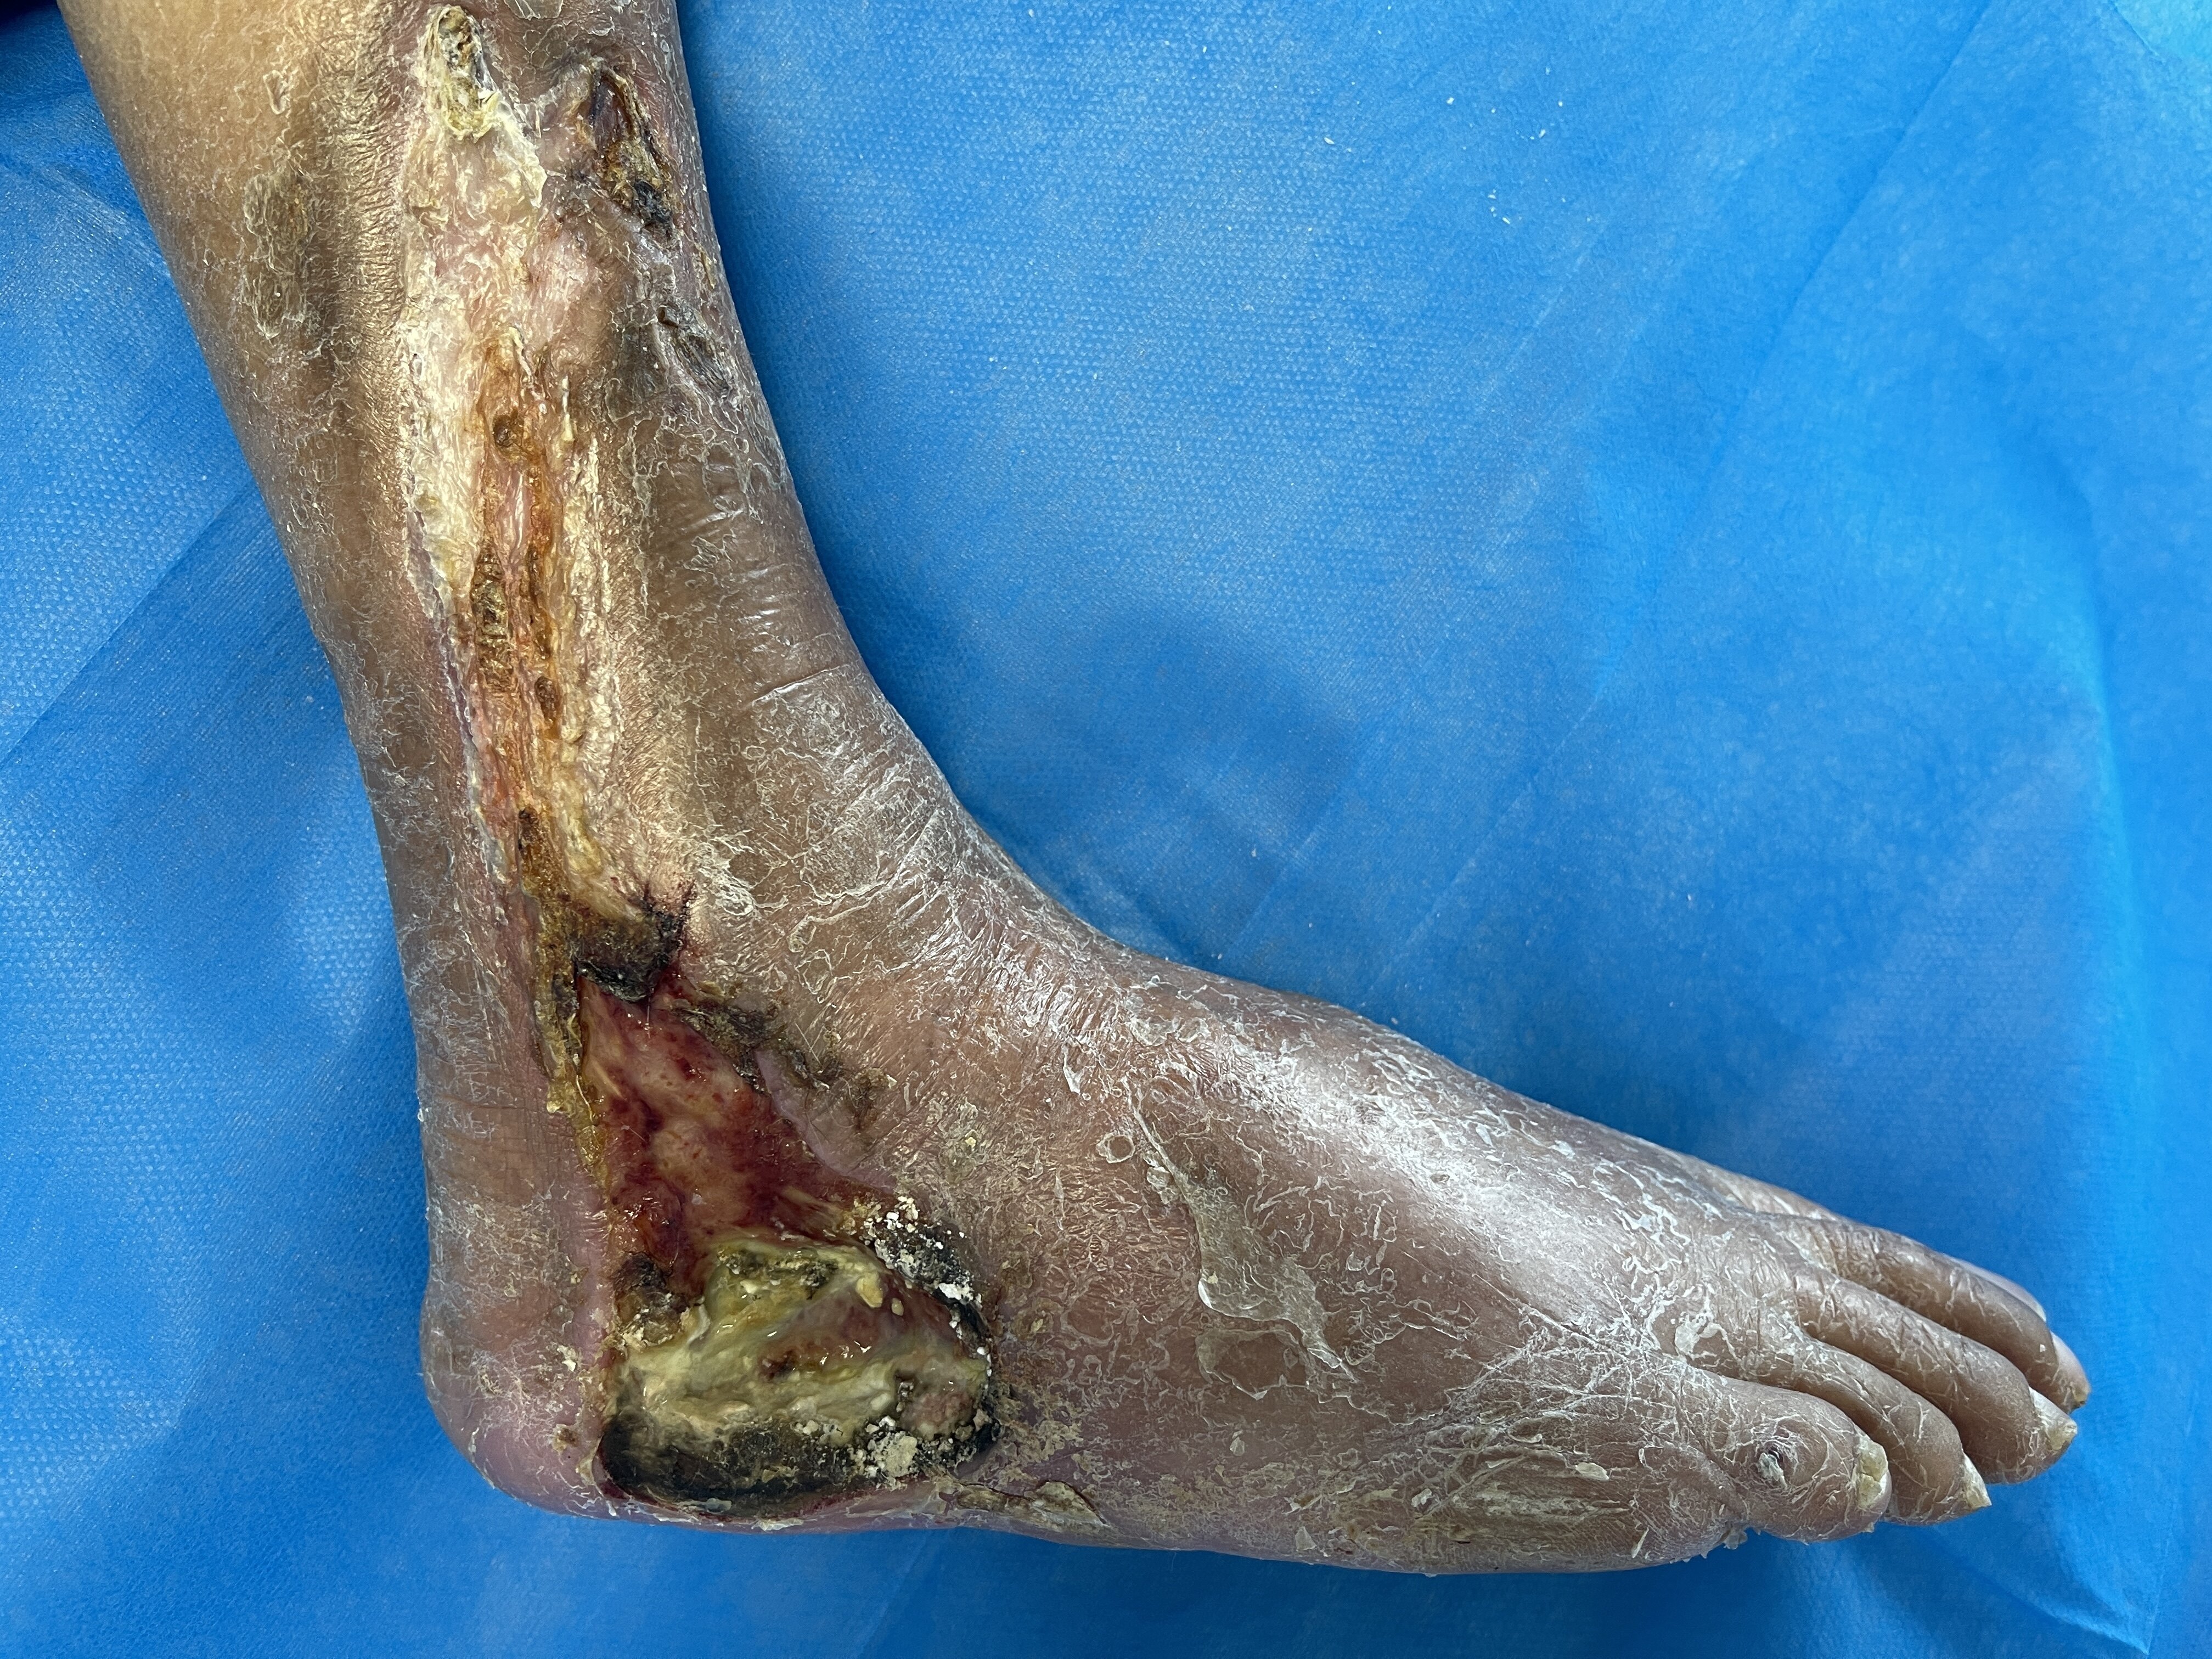

總有一些病人由于各種原因不能及時就醫(yī),令人感到遺憾……李奶奶今年81歲了,多年來身體還算硬朗。直到四五個月前,右側(cè)小腿的外側(cè)逐漸出現(xiàn)了一些破潰,老人家自己擦點藥,局部慢慢結(jié)痂了,但一直也沒有完全愈合。最近一個月,破潰越來越大蔓延到腳上,甚至傷口流出不少膿液,疼痛也越來越明顯,李奶奶夜不能寐。住院后查體發(fā)現(xiàn)李奶奶的下肢動脈閉塞非常嚴重,右側(cè)股動脈和遠端的足背動脈、脛后動脈都不能摸到搏動了。CTA檢查發(fā)現(xiàn)嚴重的血管閉塞。下肢動脈閉塞病人肢體缺血壞死是非創(chuàng)傷導致截肢的最主要原因。當您出現(xiàn)下肢發(fā)涼、行走后疼痛,甚至腳或小腿出現(xiàn)潰瘍的時候,一定要及時就醫(yī)。血管外科有各種治療方法,及時進行血運重建有望挽救這些肢體。